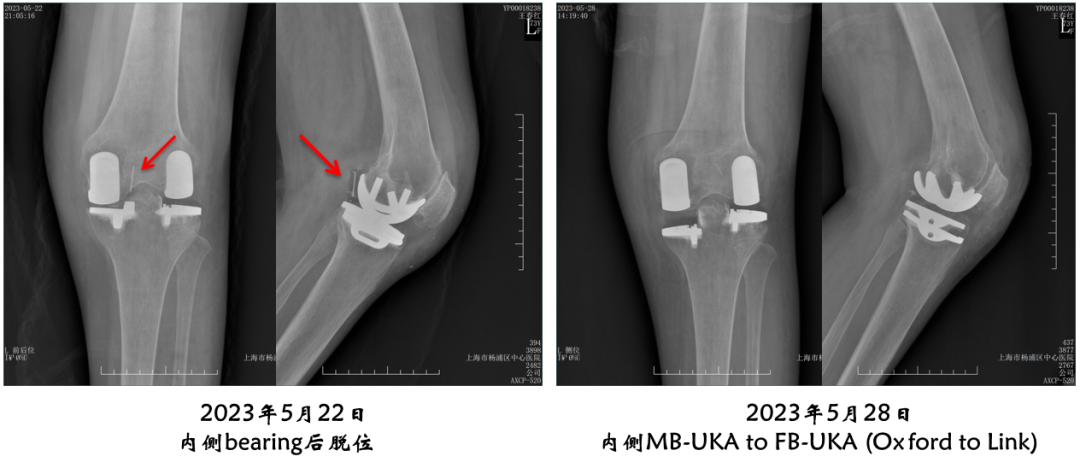

病例展示4

病例4:内侧OxfordUKA术后6.5年外侧进展性OA

病例4:Bi-UKA术后

病例4:Bi-UKA术后Bearing 后脱位的处理